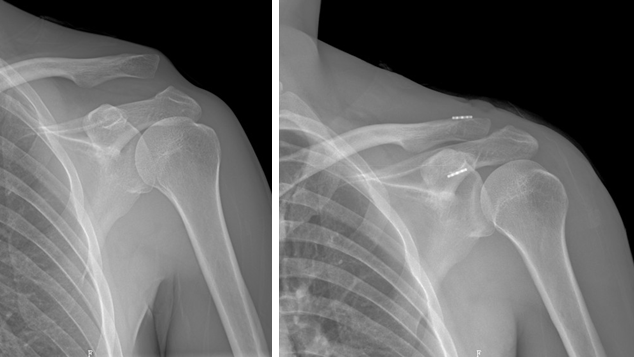

病例二:

女性83岁,跌倒致右肩关节骨折脱位,行人工肱骨头置换手术。

术前                            术后